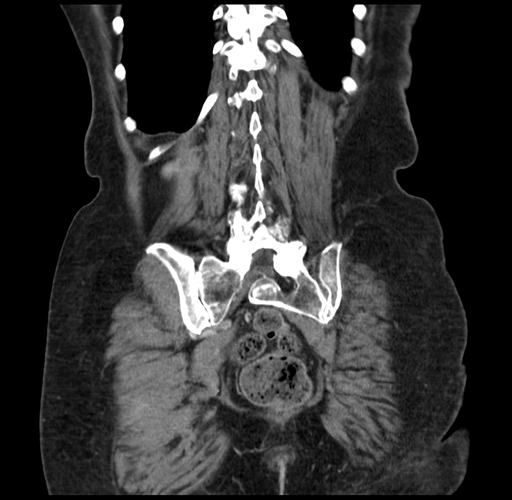

Pre-Chemo: Coronal Venous